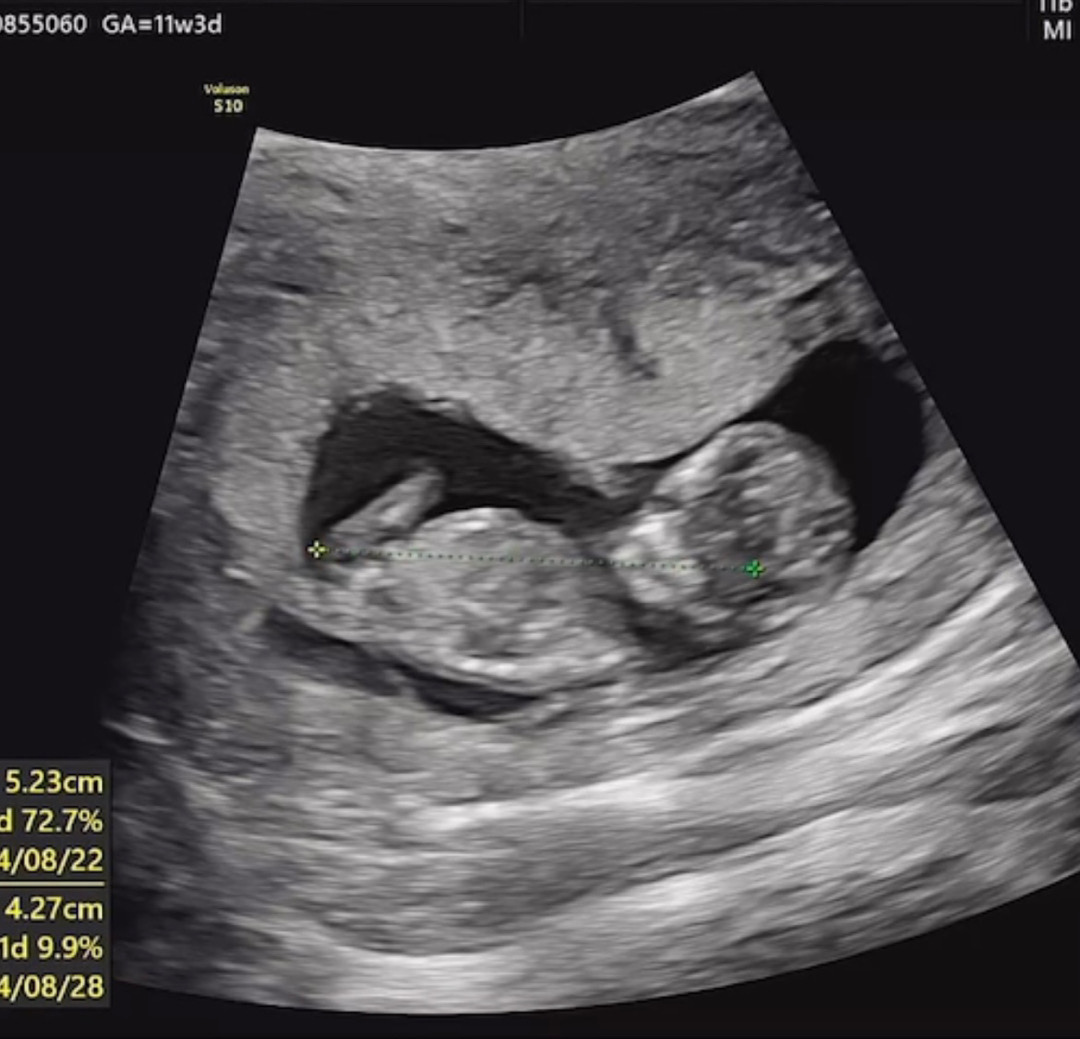

정면은 부정확하다고 하셔서 최대한 옆모습으로 올려봐요! ㅎㅎ 딸일까요??

생식기가 보여야 구분 가능해요 다리에 가려서 안보임 ㅋ